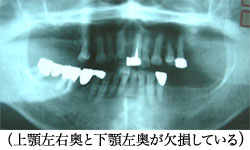

この方は御家族(脳梗塞)の介護を8年以上続けており、ご自分の身体は後回しといった状態で、初診時、糖尿病(血糖値200・毎日インシュリン注射)高血圧(降圧剤服用で140位)「奥歯のない部分には入れ歯は作ったけど取り外しが嫌で8年以上は入れずにいた」「その間、何本かの歯は自然に抜けていった」等、身体は完全にバランスを崩しており、骨質もスカスカでした。当院のインプラントの症例としては一般的なケースで、3ブロック7本のインプラントはオペ1時間程度・低侵襲で終了しました。8年以上歯がなくて前後左右高低と三次元的に狂っていた咬み合わせバランスを再構築し、かなり完成度の高い歯を提供出来たと思います。